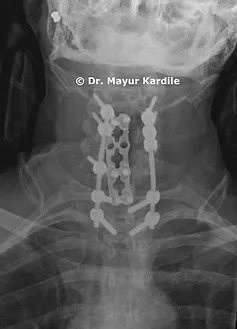

She was operated in two stages

1. C5 and C6 Corpectomy and reconstruction with a cage.

2. Posterior cervical instrumentation and fusion C3 to T1